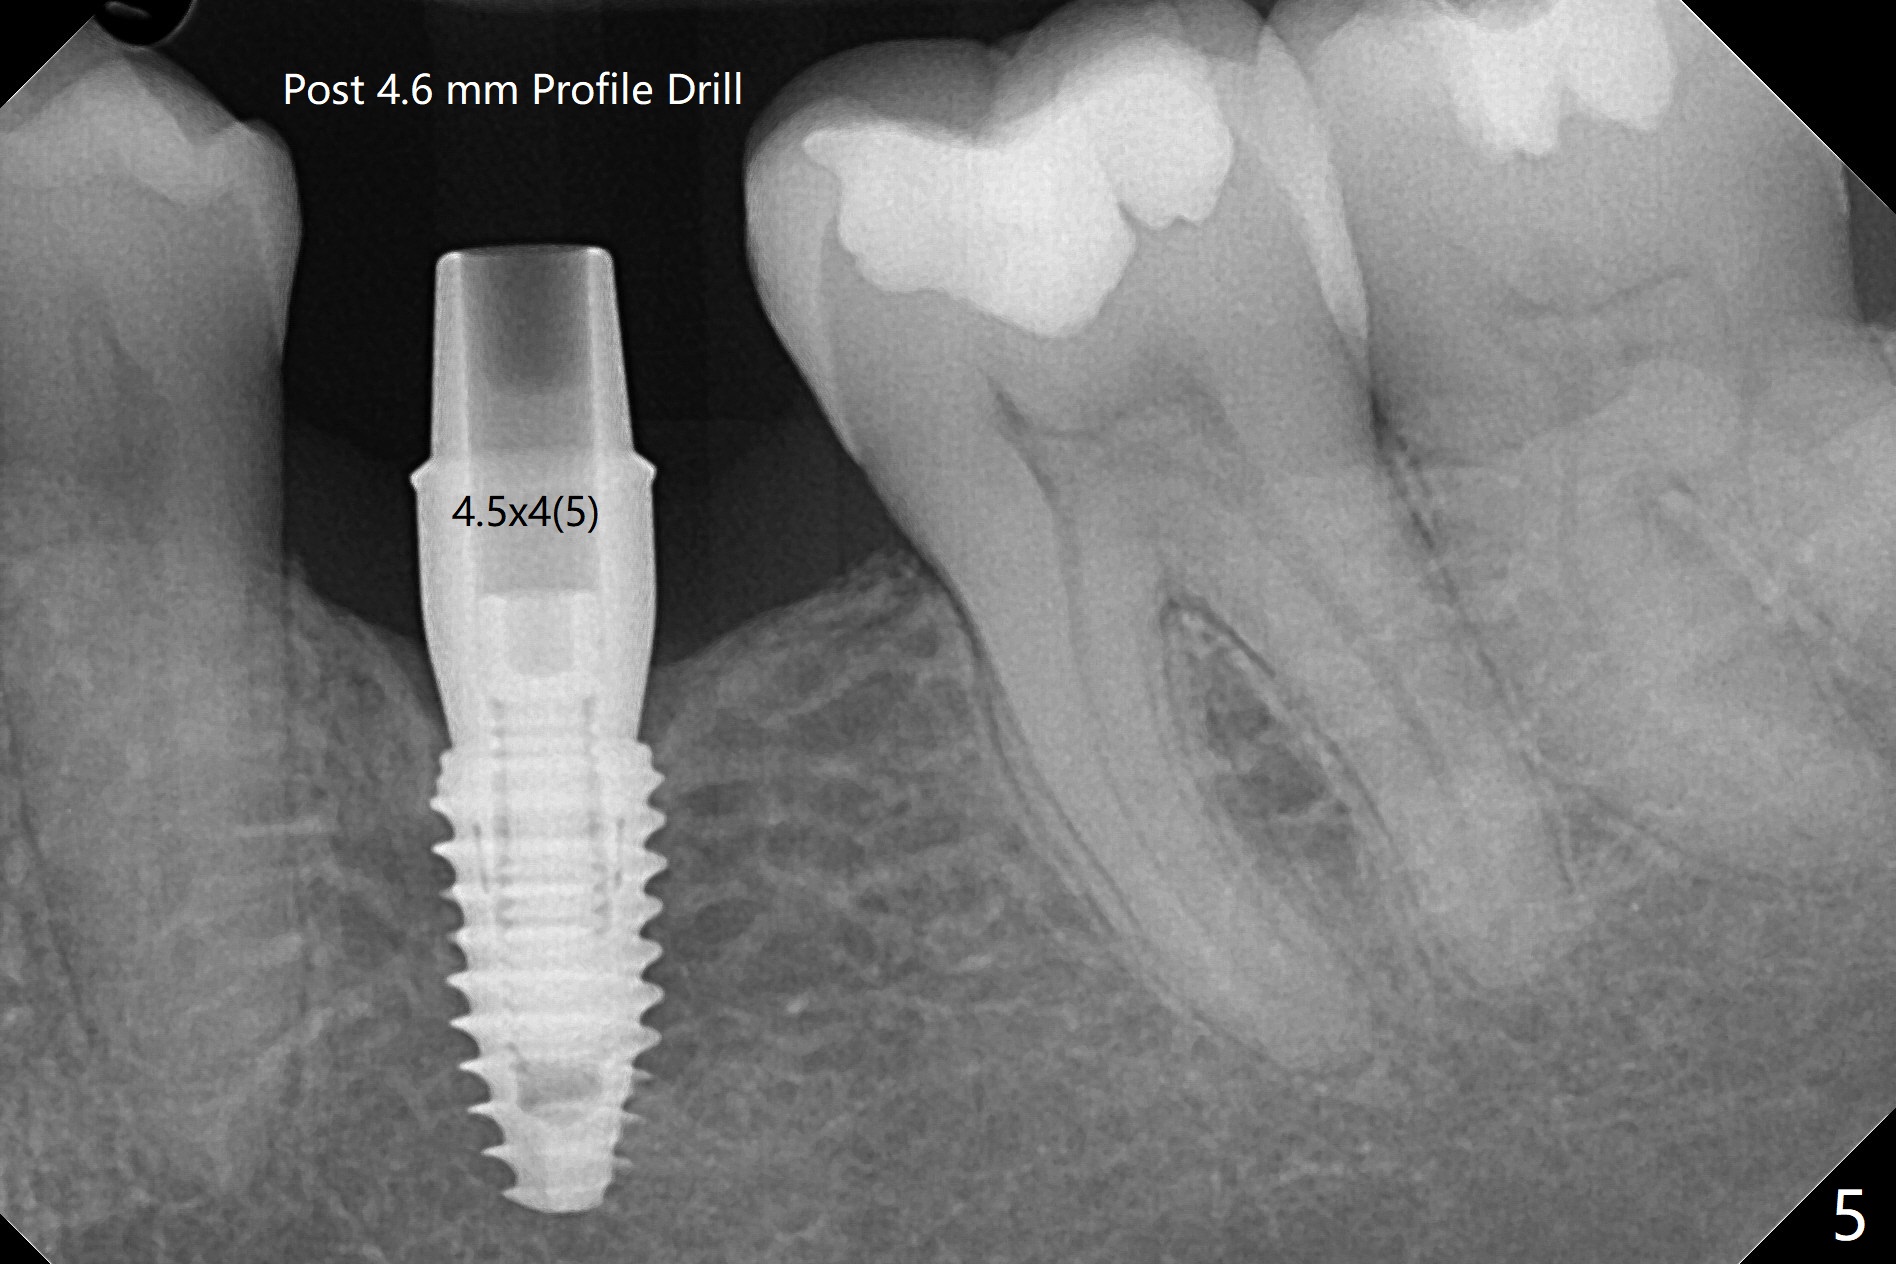

术后7个月左下4毫米修复基台无法就位(图四:箭头),局麻下使用4.6毫米Profile钻头后(去除软硬组织阻挡),4.5毫米修复基台顺利就位(图五)。右下第一次手术已经应用Profile钻头,牙槽嵴吸收,所以放置4.5毫米修复基台没问题(图六)。第一次手术应该使用Profile钻头。